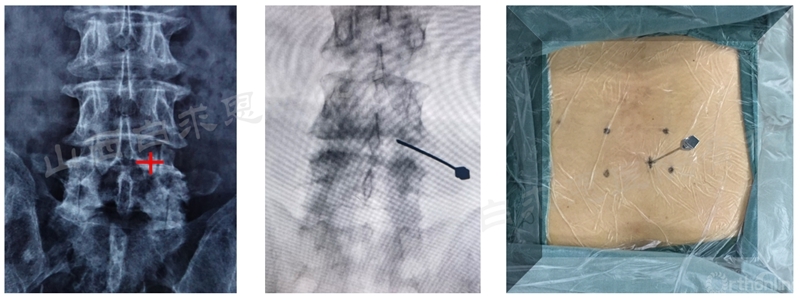

(1)穿刺定位

(2)镜下定位

SAP:Superior articular process(下关节突);IAP:Inferior articular process(上关节突);LF:Ligamentum flavum(黄韧带)